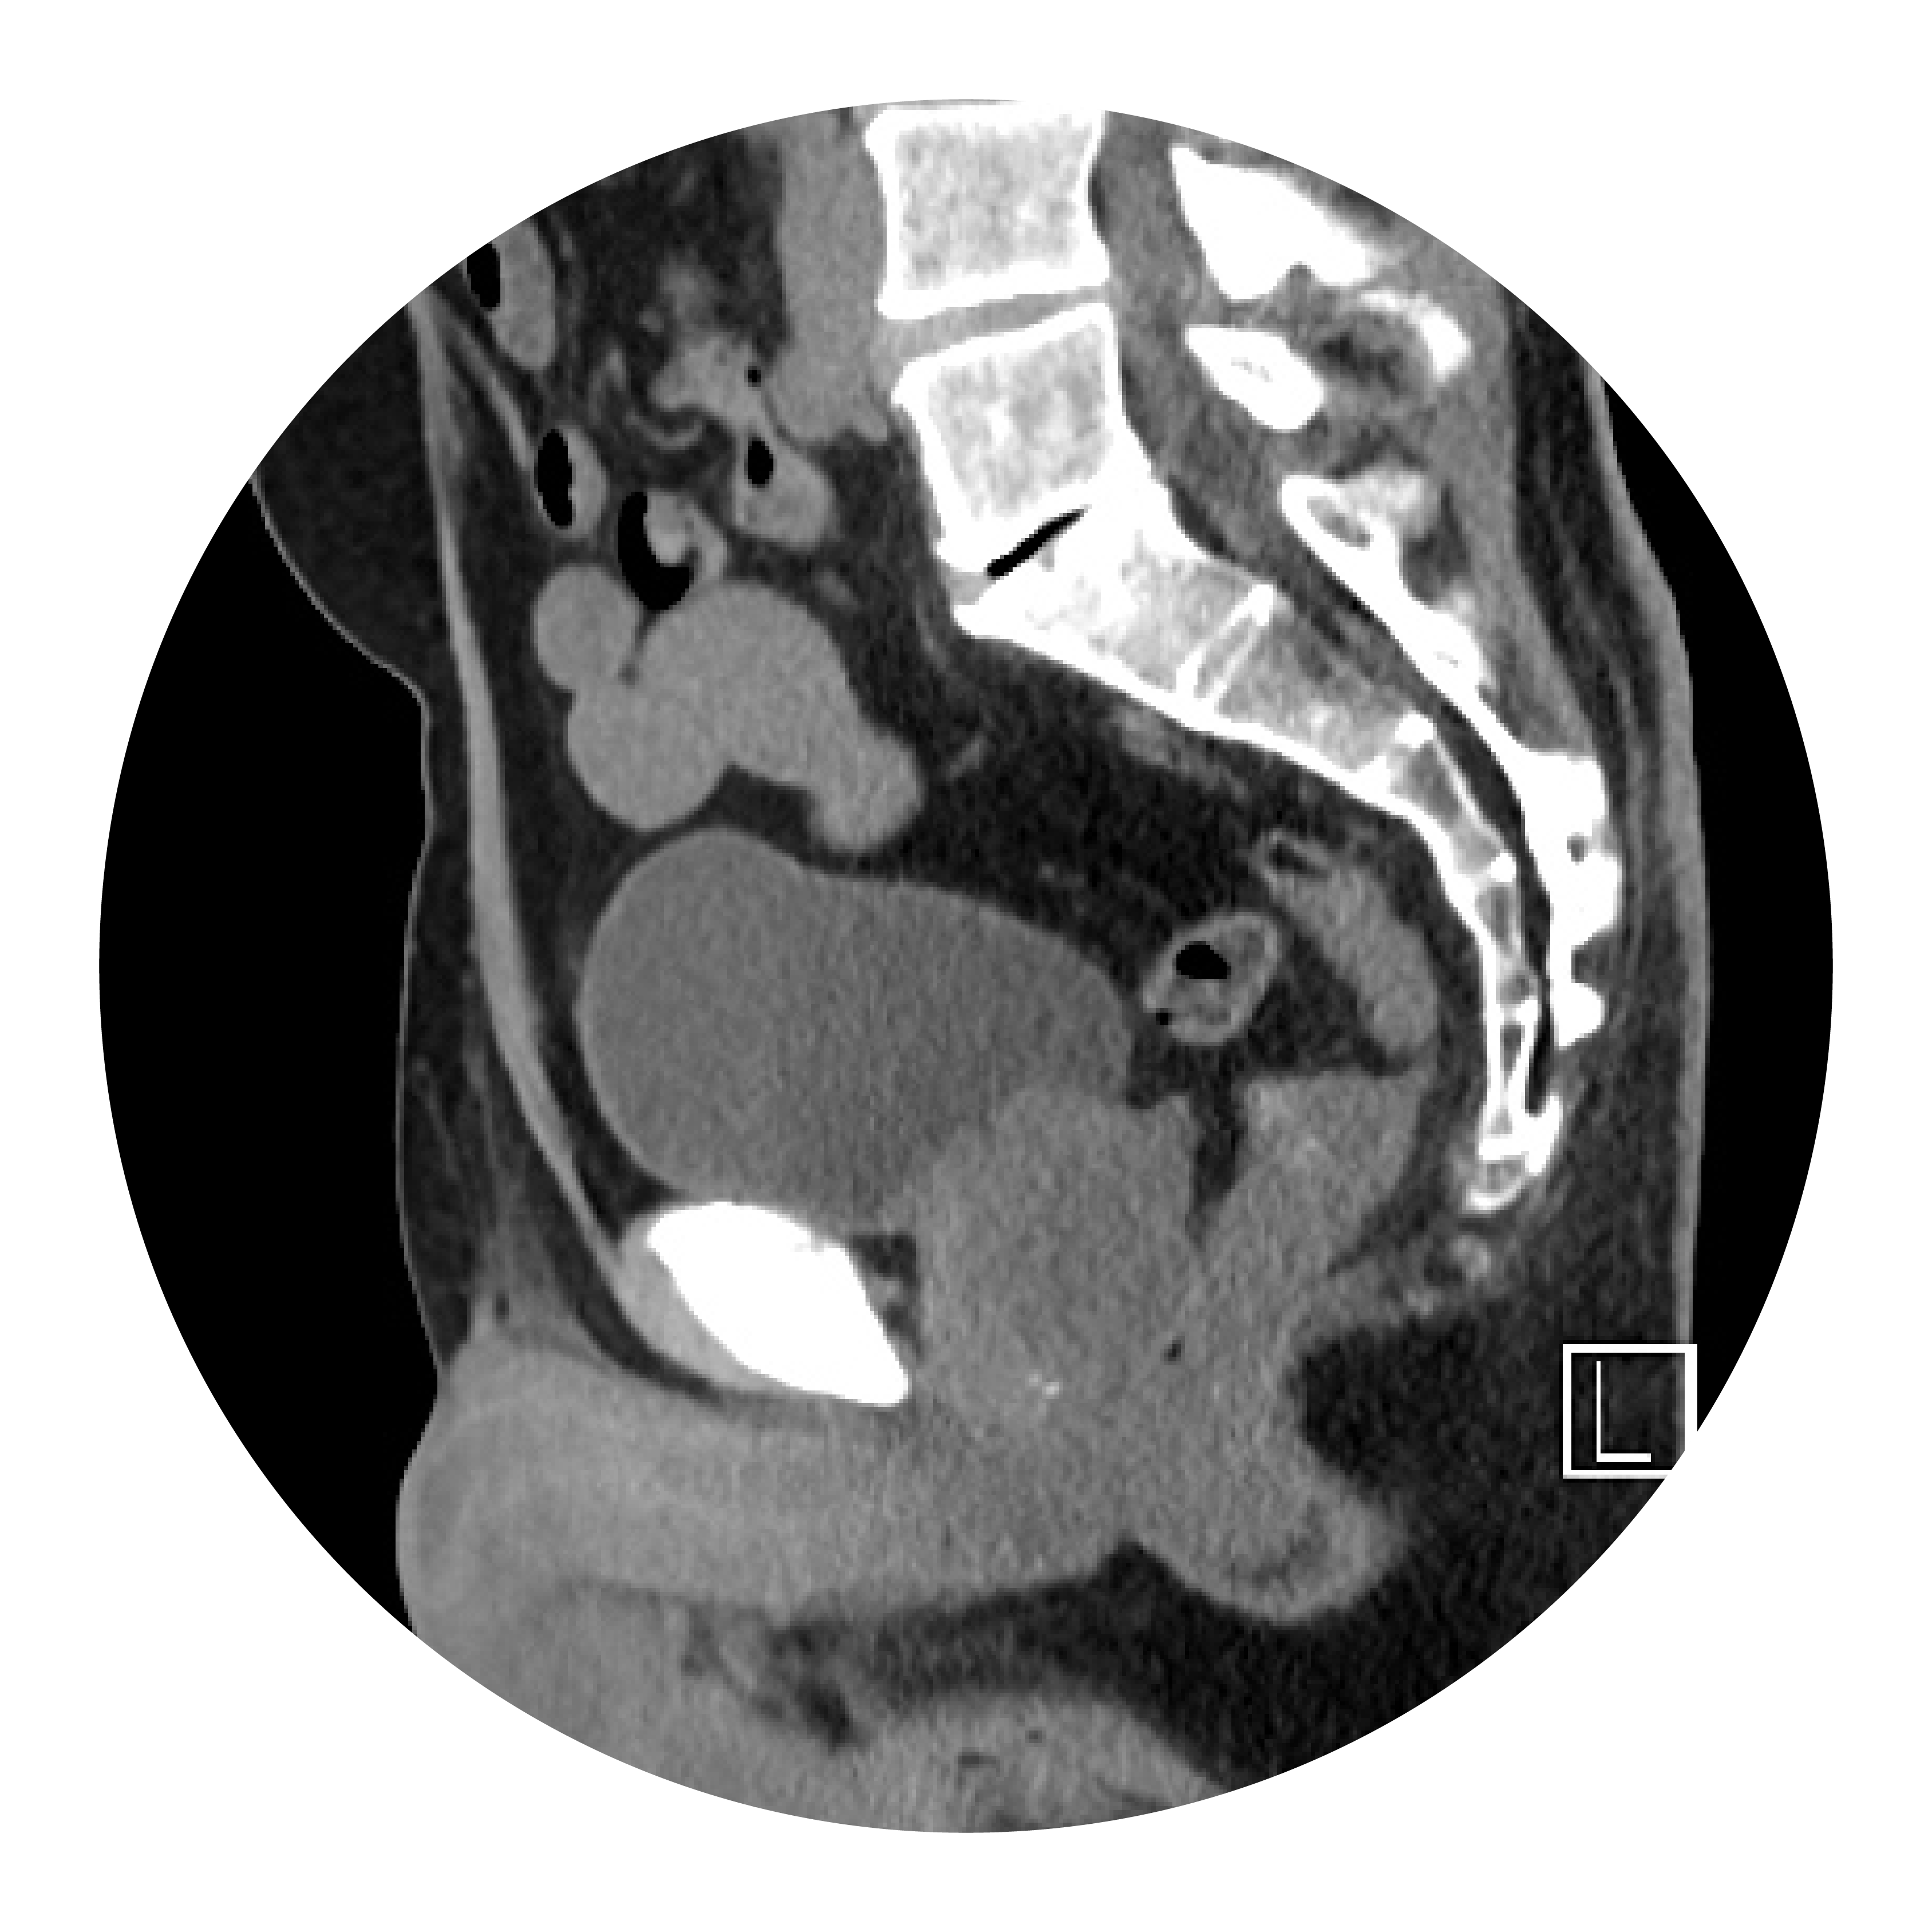

Tomografía computarizada (TC)

Durante una exploración por TC, se utiliza una computadora conectada a una máquina de rayos X para obtener una serie de imágenes de rayos X detalladas de áreas del interior del cuerpo desde diferentes ángulos. Se inyecta un tinte específico que se desplaza hacia la vejiga, e ilumina las células cancerosas para que puedan verse en las imágenes radiográficas. El tinte de contraste es un líquido especial que se utiliza durante una TC para ayudar a los médicos a ver ciertas áreas del cuerpo con mayor claridad.¹‚³

Urografía por tomografía computarizada (TC)

La urografía por TC es una TC de las vías urinarias, que incluye los riñones, los uréteres y la vejiga. Proporciona información detallada sobre el tamaño, la forma y la posición de cualquier tumor en las vías urinarias, incluida la vejiga. También puede revelar la presencia de ganglios linfáticos agrandados que podrían contener cáncer, así como otros órganos en el abdomen y la pelvis.¹